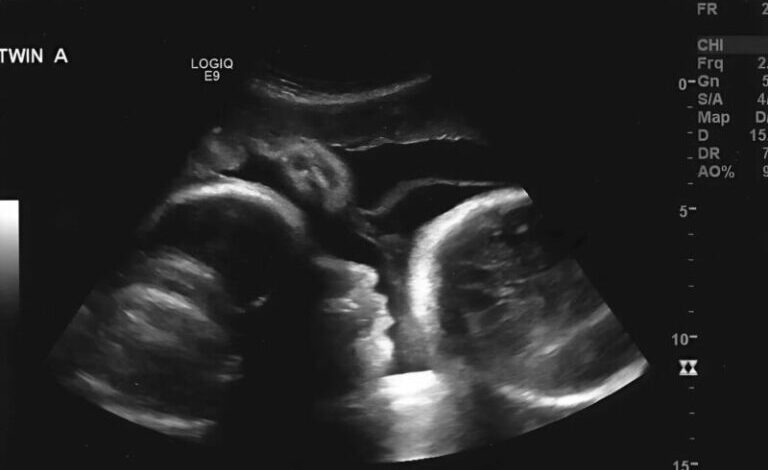

This second stage of medical assessment proved to be important in clarifying her condition. Specialists performed more comprehensive imaging and laboratory tests to better understand the underlying cause.

The results revealed that the symptoms were not related to the initial assumptions but instead indicated a more serious medical condition requiring prompt and structured treatment.

Modern diagnostic tools such as ultrasound, CT scans, and laboratory testing have significantly improved the ability of doctors to identify conditions accurately and early.